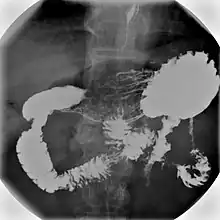

Normal barium swallow fluoroscopic image, showing the ingested barium sulfate being induced down the oesophagus by peristalsis. | |

An upper gastrointestinal series, also called a barium swallow, barium study, or barium meal, is a series of radiographs used to examine the gastrointestinal tract for abnormalities. A contrast medium, usually a radiocontrast agent such as barium sulfate mixed with water, is ingested or instilled into the gastrointestinal tract, and X-rays are used to create radiographs of the regions of interest. The barium enhances the visibility of the relevant parts of the gastrointestinal tract by coating the inside wall of the tract and appearing white on the film. This in combination with other plain radiographs allows for the imaging of parts of the upper gastrointestinal tract such as the pharynx, larynx, esophagus, stomach, and small intestine such that the inside wall lining, size, shape, contour, and patency are visible to the examiner. With fluoroscopy, it is also possible to visualize the functional movement of examined organs such as swallowing, peristalsis, or sphincter closure. Depending on the organs to be examined, barium radiographs can be classified into "barium swallow", "barium meal", "barium follow-through", and "enteroclysis" ("small bowel enema"). To further enhance the quality of images, air or gas is sometimes introduced into the gastrointestinal tract in addition to barium, and this procedure is called double-contrast imaging. In this case the gas is referred to as the negative contrast medium. Traditionally the images produced with barium contrast are made with plain-film radiography, but computed tomography is also used in combination with barium contrast, in which case the procedure is called "CT enterography".[1]

Mechanism

Barium sulfate is swallowed and is a radio opaque substance that does not allow the passage of X-rays. As a result, areas coated by barium sulfate will appear white on an X-ray film. The passage of barium sulfate through the gastrointestinal tract is observed by a radiologist using a fluoroscope attached to a TV monitor. The radiologist takes a series of individual X-ray images at timed intervals depending on the areas to be studied. Sometimes medication which produces gas in the gastrointestinal tract is administered together with the Barium sulfate. This gas distends the gastrointestinal lumen, providing better imaging conditions and in this case the procedure is called double-contrast imaging.[9]

A thick barium mixture is swallowed in supine position and fluoroscopic images of the swallowing process are made. Then several swallows of a thin barium mixture are taken and the passage is recorded by fluoroscopy and standard radiographs. The procedure is repeated several times with the examination table tilted at various angles. A total of 350–450 mL of barium is swallowed during the process.[14][15] Normally, 90% of ingested fluid should have passed into the stomach after 15 seconds.[16]